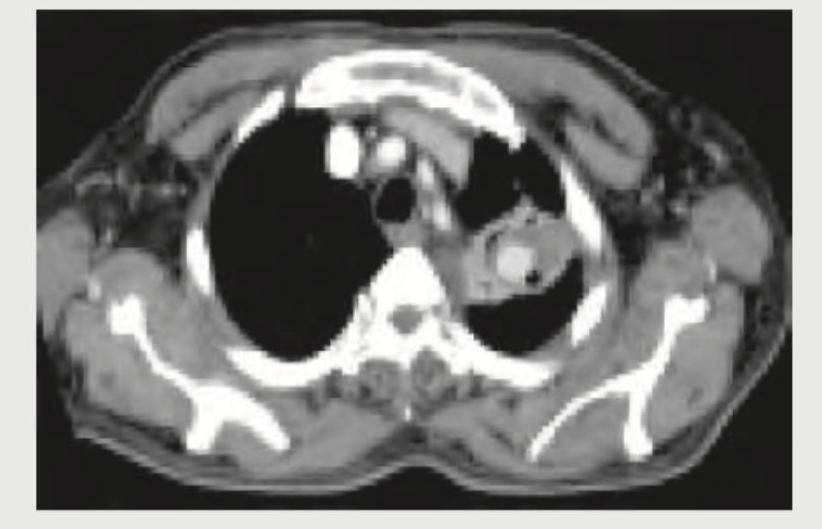

The given contrast enhanced CT scan chest shows presence of:

Explanation: ***Cavity*** - The CT scan image clearly shows a **well-defined, air-filled lucency within a consolidation** in the left lung, which is characteristic of a cavity. - The presence of an enhancing rim around the lucency suggests an **active inflammatory or neoplastic process** forming the cavity. *Pneumonia* - While pneumonia can cause consolidation, the image shows a distinct **focal air-filled space** within the area of consolidation, which is not typical for uncomplicated pneumonia. - Pneumonia would usually appear as a **homogenous or heterogeneous opacification** of the lung parenchyma, without such a clear cavity. *Lung contusion* - Lung contusion is typically associated with **trauma** and appears as **patchy, non-segmental ground-glass opacities or consolidation**. - It does not usually form a well-defined cavity with an enhancing wall, as seen in the image. *Segmental collapse* - Segmental collapse (atelectasis) would present as a **volume loss in a lung segment**, often with displacement of fissures or mediastinal structures, and increased attenuation of the collapsed lung. - The image shows a **focal lesion with internal lucency**, not a collapsed segment of lung, and there is no clear evidence of volume loss.